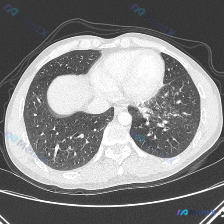

看到这个提问,我整理了一下完整的分析思路,分享给大家。 病例影像核心信息 这是一张胸部CT肺窗横断面图像,核心发现: 1. 双肺透亮度尚可,可见双肺多发异常密度影(Airspace opacity),呈弥漫分布,中下肺野及肺外周区更明显 2. 病灶为多发微结节、小斑片状影,部分边缘模糊,呈腺泡/小叶...